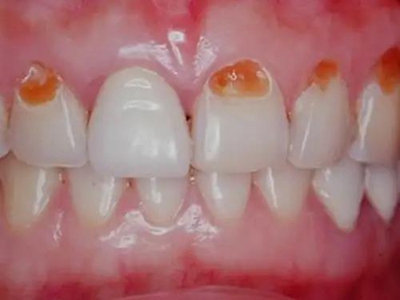

牙齿

斑

酸蚀症牙面缺一块有黄色斑块图

酸蚀症患者牙齿表面出现大片黄色或淡黄色斑块,轻微凹陷,具体形态不规则,周围会有针尖、粟状小斑点,由于长期饮用可乐、果汁等酸性饮料引起。